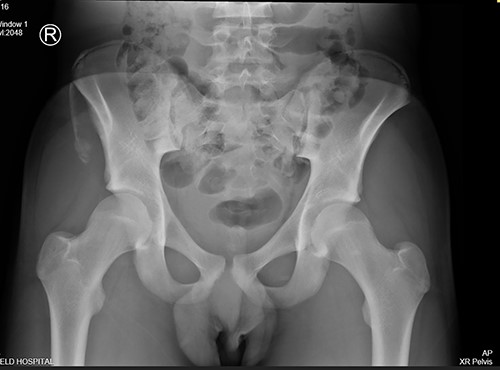

The anterior–posterior plain film X-Ray of pelvis demonstrated an avulsion fracture of the right ASIS and IC apophysis with 1.5 cm displacement (Fig. 1). Lateral view of the hip showed no extension into the joint. There was no radiological evidence of chronic overuse or previous injury. Computed tomography (CT) imaging was performed to better identify the injury; 3D volume reconstruction clearly demonstrated the unique fracture pattern of an ASIS avulsion in addition to an avulsion of the distal iliac apophysis extending ~5 cm with the described displacement (Figs 2–4).

3D reconstruction of tomographic CT scan illustrating avulsion fracture of ASIS and IC apophysis with its latero-inferior displacement (R - Right, L - Left, A - Anterior).